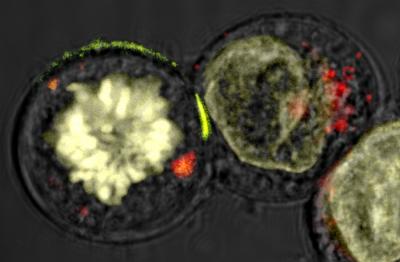

Scientists reveal in more detail than ever before how white blood cells kill diseased tissue using deadly granules, in research published today in PLoS Biology .

The researchers, from Imperial College London and the University of Oxford, used 'optical' laser tweezers and a super-resolution microscope to see the inner workings of white blood cells at the highest resolution ever. The researchers describe how a white blood cell rearranges its scaffolding of actin proteins on the inside of its membrane, to create a hole through which it delivers deadly enzyme-filled granules to kill diseased tissue.

The new visual resolution of NK cell action is a result of a novel imaging technique developed in collaboration with physicists at Imperial, and the use of a super high-resolution microscope at the University of Oxford. The researchers immobilised an NK cell and its target using a pair of 'optical' laser tweezers so that the microscope could capture all the action at the interface between the cells. They then watched inside the NK cell as the actin filaments parted to create a tiny portal and the enzyme-filled granules moved to the portal, ready to pass out of the NK cell and onto the target to kill it.

The contact between an NK cell and its target is only about a hundredth of a millimetre across and the miniscule actin proteins and granules change position continuously over the few minutes from initial contact until the target is killed. The microscope has to be able to capture images quickly enough and in high enough visual detail in order to reveal their activity.

Professor Ilan Davis, a Wellcome Trust Senior Fellow at the University of Oxford, whose group applies super resolution technique to basic cell biology research said: "Our microscope has given us unprecedented views inside living NK cells capturing a super-resolution 3D image of the cell structures at twice the normal resolution of conventional light microscope. This method, developed at University of California San Francisco by Professor John Sedat, maximizes the amount of light captured from the specimen while minimizing the amount of stray light inside the instrument."